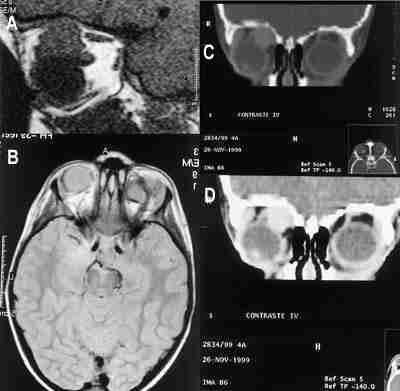

53-14.jpg (14744 bytes)

Figuras 14a y b. Resto tumoral activo de retinoblastoma que se diferencia en secuencia T1 con gadolínio del componente óseo, para realizar mediciones previa a la colocación de la placa radioactiva.

La sección de Oftalmología infantil y la sección de Neurorradiología del Hospital Universitario La Paz, hemos realizado un estudio prospectivo mediante RM para valorar la existencia o no de revascularización en función del grado de captación de Gd en 39 niños (20 niñas y 19 niños) sometidos a enucleación o evisceración uni o bilateralmente y de edades comprendidas entre los 3 meses y los 2 años por diferentes patolo gías de base, colocando en 10 casos prótesis de MEDPOR y en 29 niños prótesis de hidroxiapatita (en un caso de forma bilateral). Se realizaron secuencias potenciadas en T1, con saturación grasa y reconstrucciones axiales y sagitales de 3 mm con matriz de alta resolución antes y después de la administración de gadolinio. La RM nos permitió evaluar diferentes parámetros como el grado de captación (sinónimo de revascularización del implante), la forma de captación (homogénea o heterogénea), el lugar de comienzo (anterior o posterior), la existencia o no de captación extraprótesis como índice de infección periprótesis y la presencia o no de líneas que sugieran fisuras o alteraciones intrínsecas de la prótesis. Estos parámetros fueron comparados con la evolución y el estado de la prótesis en el acto quirúrgico de la colocación del vástago, evaluando el grado de correlación entre los hallazgos en la RM y los datos clínicos y quirúrgicos (figura 15).

53-15.jpg (13343 bytes)

Figuras 15a, b, c y d. Secuencias T1 con gadolínio intravenoso y saturación grasa de prótesis porosas. Captación completa de la prótesis en (a). Falta la vascularización anterior en la prótesis (b, c). Línea de fractura de la prótesis (d).

Los resultados de nuestro estudio muestran una forma de vascularización bastante constante, empezando por el polo posterior, con un patrón homogéneo, y quedando la parte anterior como última zona para vascularizar. Esto podría explicar la aparición de exposiciones anteriores y malas implantaciones de vástagos en los casos de prótesis sin buena vascularización anterior. Por ello, es especialmente importante que sea prácticamente completa antes de la colocación del vástago, o, por lo menos, la de la región anterior. Respecto al tiempo de esta revascularización, nuestros resultados coinciden con los referidos en la literatura, siendo necesario casi un año en el caso de las prótesis HA para lograr un 75-80 por ciento y un tiempo algo menor para las prótesis MEDPOR. Son llamativas las diferencias en la sensibilidad de la RM para las prótesis de MEDPOR y las de HA, significativamente menor en la primera. Hay que tener en cuenta, sin embargo, varios hechos a la hora de evaluar estos resultados como el escaso número de prótesis de MEDPOR estudiadas con RM por el momento (solo diez) y el hecho de que en todos los casos en los que ha existido una mala correlación clínico-radiológica el recubrimiento era de esclera. Quizá este tipo de recubrimiento dificulta la valoración de la captación. También puede ser que el MEDPOR pueda dar lugar a más variabilidad en la forma de captación. De hecho, el patrón y la forma de evolución de la captación son menos constantes en el MEDPOR que en la HA.

En conclusión, y de acuerdo con otros trabajos, la RM es un método útil y de alta fiabilidad en el control de las prótesis sobre todo de HA. Asimismo, la RM es especialmente útil para la detección de complicaciones en ambos tipos de prótesis (36-39).